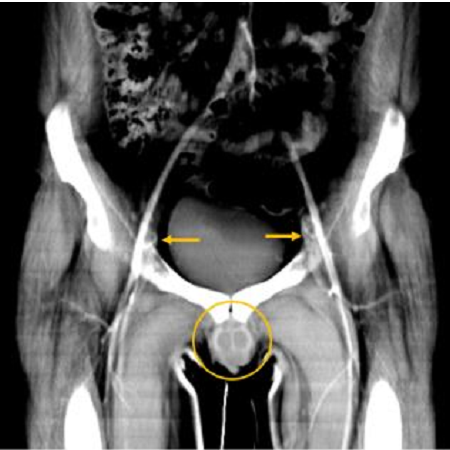

O painel A mostra uma reconstrução tomográfica computadorizada pré-operatória da extensão da lesão; o B mostra o enxerto; o C mostra o enxerto antes do procedimento, juntamente com imagens clínicas dos dias 8, 15 e 340 do pós-operatório. (Imagem: Redett et al., NEJM, 2019)